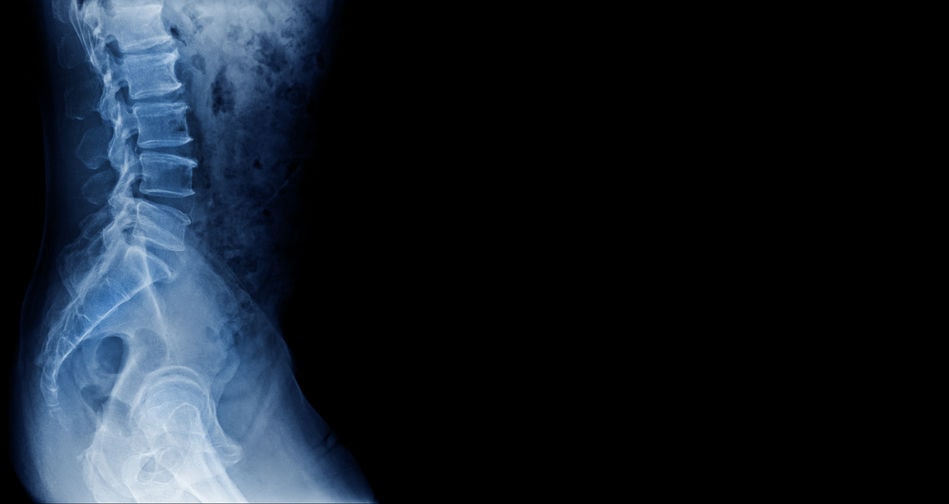

Hiperextensión lumbar

Un movimiento a evitar es la hiperextensión forzada de la espalda. La hiperextensión se debe principalmente al movimiento de la zona lumbar. Boca abajo este movimiento alcanza 20º, aumentando hasta los 30º cuando estamos de pie.

La hiperextensión dorso lumbar forzada aumenta la presión intradiscal, sobrecarga las articulaciones posteriores de las vértebras y produce lesiones por contacto entre las apófisis espinosas.

Hiperflexión lumbar

La hiperflexión del tronco sobrecarga los discos L4-L5-S1, pudiéndose producir hernias discales. Cuando tratamos de doblar en exceso la columna, por ejemplo al realizar estiramientos y tratar de tocar el suelo con las manos muchas veces provocamos un aumento excesivo de la cifosis forzándose en exceso las estructuras dorsales.